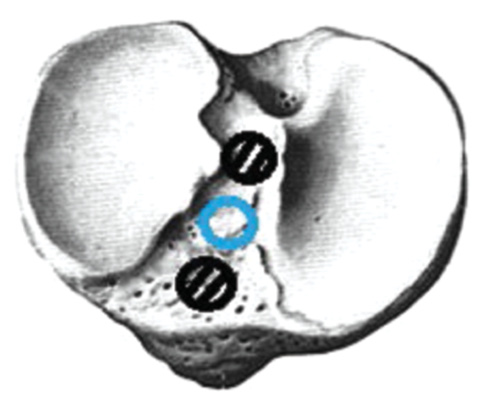

In addition to the inappropriate topical location of the channels in the femoral condyle in 6 (6.5%) patients, another problem occurred, i.e., the channel had a large (>12 mm) diameter. In such cases, fixators (Milagro) were additionally used to center the autograft in the channel from 2–3 sides (Fig. 12). Control examination of the patients was performed 3, 6, and 12 months after the surgery.

Fig. 12. Canal diameter more than 12 mm, graft centering using 2–3 screws.